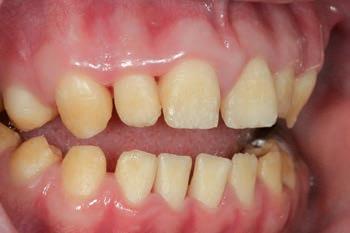

Clinical case

The patient was an 18-year-old male with a confirmed family history of Xlinked AI, who was otherwise in good health and non-smoking. Upon initial clinical presentation, a low-caries-risk, complete adult dentition from second molar to second molar was present, which was globally affected by pitted, hypoplastic and hypomineralised AI, dento-alveolar disproportion and an unusual generalised open occlusion, characterised by one occlusal contact at the right first molar region in the maximum intercuspation position (MIP). Historical paediatric management of the dentition involved placement of stainless steel crowns at the first permanent molar sites to protect the emerging dentition from post-eruptive breakdown and loss of occlusovertical dimension during the mixed dentition phase.6 On adult presentation, all but the UR6 stainless steel crown remained intact. Oral hygiene was poor, with evidence of plaque-induced chronic gingivitis (Figure 1). The patient reported experiencing severe, widespread hypersensitivity upon hot, cold, osmotic and masticatory stimuli, and feeling aesthetically self-conscious. The patient was seeking comprehensive fixed prosthodontic care and was well informed about the nature of such treatment, having witnessed his elder siblings undergo similar treatment.

1: The patient’s initial situation on clinical presentation to the tertiary care referral centre. The dentition is globally af fected by amelogenesis imperfecta, associated with dentoalveolar disproportion and an unusual presentation of open occlusion.